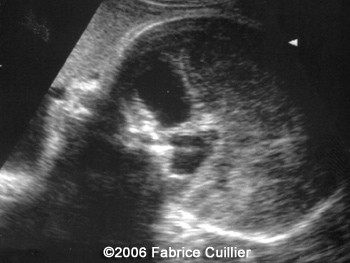

The following images are obtained in a 3rd trimester fetus:

The final diagnosis was: Arachnoid cyst